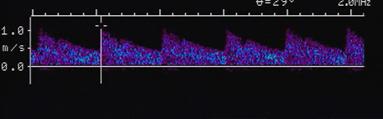

Explain the waveform of the ECA

high resistant

steep forward stroke

Forward flow during systole, low or reverse diastolic component